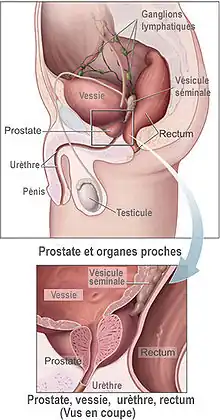

Le cancer de la prostate est un cancer fréquent touchant la prostate, une glande de l'appareil reproducteur de l'homme. Le cancer se développe à partir des tissus de la prostate quand des cellules y mutent et se multiplient de façon incontrôlée. Celles-ci peuvent ensuite s'étendre (se métastaser) en migrant de la prostate jusqu'à d'autres parties du corps, particulièrement les os et les ganglions lymphatiques du pelvis.

Le cancer entreprend la portion périphérique de la glande, au contraire de l'hypertrophie prostatique bénigne qui intéresse la zone centrale, périurétrale.

Bilan d'extension

L'extension de la maladie doit être déterminée au mieux afin d'adapter les traitements. Il faut donc rechercher la présence de métastases osseuses, pulmonaires et hépatiques, sachant que les métastases osseuses sont les plus fréquentes. Il faut rechercher des métastases ganglionnaires dans le bassin et le rétropéritoine (autour de l'aorte abdominale). il faut enfin essayer de préciser l'extension de la tumeur dans la prostate, en particulier savoir si celle-ci dépasse la capsule prostatique ou non.

- T3 : extension du cancer aux tissus périphériques (franchissement de la capsule prostatique).

- T3a : franchissement de la capsule

- T3b : envahissant une ou deux vésicules séminales

- T4 : extension aux organes adjacents : vessie, rectum, paroi pelvienne.

Chirurgie

Elle repose sur la prostatectomie, dite radicale ou totale. Elle consiste en l'ablation de la prostate et des vésicules séminales et peut être précédée d'un prélèvement des ganglions de drainage de la prostate. La chirurgie peut être réalisée par voie ouverte (incision chirurgicale au niveau de l'abdomen ou au niveau du périnée), par voie cœlioscopique abdominale, ou bien à l'aide de l'appareil Da Vinci ; la chirurgie est réservée aux cancers localisés à la prostate et offre de grandes chances de guérison si le cancer est effectivement localisé et peu ou moyennement agressif (agressivité estimée par le score de Gleason) ; elle peut entraîner une incontinence urinaire, le plus souvent temporaire et des troubles de l'érection. Il n'y a pas de supériorité d'une technique par rapport à une autre en ce qui concerne les résultats carcinologiques et les résultats fonctionnels urinaires et sexuels.